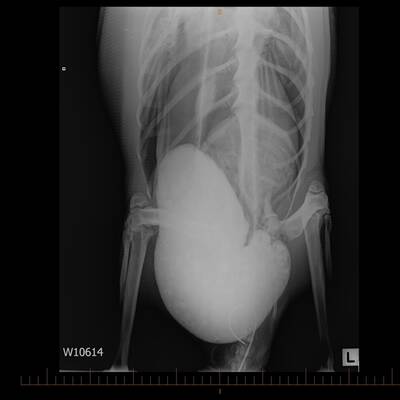

Der Sand bekam dem Kaiserpinguin aber gar nicht , sein Magen musste mehrfach im Zoo von Wellington ausgespült werden.

Die Neuseeländer nannten das Tier „Happy Feet“ , nach einem Pinguin aus einem Trickfilm. Zuerst sah es nicht gut aus für „Happy Feet“, er musste sogar ins künstliche Koma geschickt werden. Aber das Tier er­holte sich überraschend schnell, als der Magen von Sand und Treibholz befreit war. Rund 30 Deka Mist wurde entfernt. Dann war der Vogel wieder forsch.